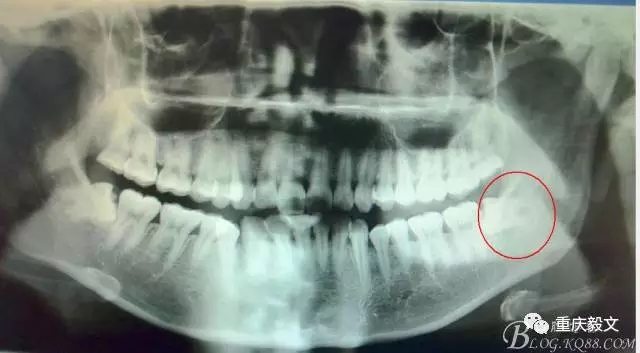

患者、李xx、女、20歲,主訴:左側(cè)下后牙牙齦不適數(shù)天。專科檢查:38水平位、牙冠萌出黃豆大小,頰側(cè)牙齦未見(jiàn)明顯紅腫,全景片檢查:38水平位、雙根、分叉大,37遠(yuǎn)中頸部未見(jiàn)齲壞。診斷:38中位水平阻生 治療計(jì)劃:微創(chuàng)拔除38。術(shù)前與患者充分溝通,告訴患者采用無(wú)痛sta阻滯麻醉加不切開(kāi)翻瓣拔除。患者同意手術(shù)方案,簽知情同意書。

圖1.全景片檢查:38水平位、雙根、分叉大。